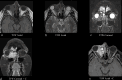

The lacrimal gland is a bilobed serous gland located in the superolateral aspect of the orbit. Lacrimal system pathologies can be broadly divided into pathologies of the lacrimal gland and those of the nasolacrimal drainage apparatus. These include distinct congenital, infectious, inflammatory, and benign, indeterminate, and malignant neoplastic lesions. Trauma and resultant fractures affecting lacrimal drainage apparatus is not part of this review; only non-traumatic diseases will be discussed. CT is the initial modality of choice because of its ability to delineate lacrimal system anatomy and demonstrate most lacrimal drainage system abnormalities and their extent. It also assesses bony architecture and characterizes any osseous changes. MRI is helpful in further characterizing these lesions and better assessing involvement of the surrounding soft tissue structures. In this pictorial review, we will review the anatomy of the lacrimal system, describe CT/MRI findings of the common and uncommon lacrimal system abnormalities and discuss relevance of imaging with regards to patient management.